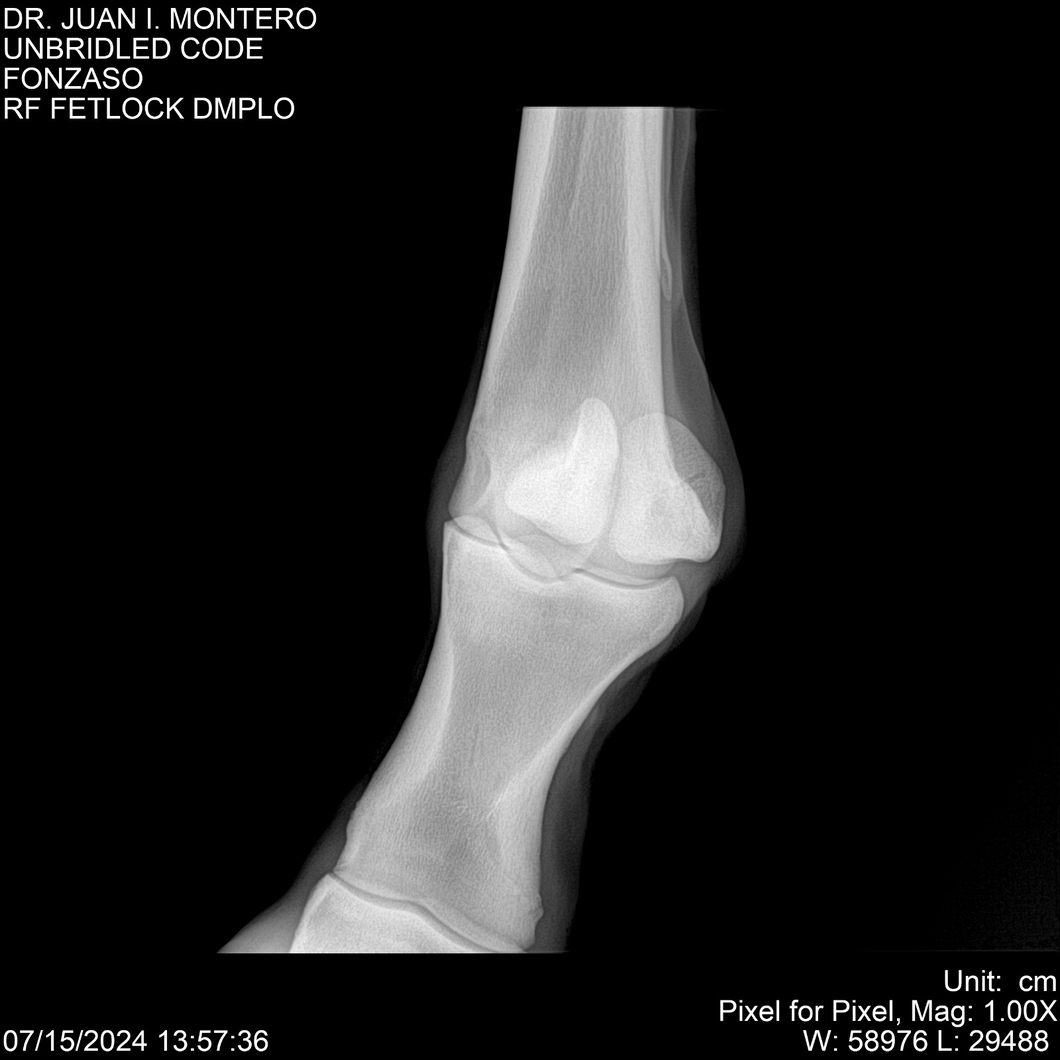

• Empresa: Abelenda N. R., Walter Hugo